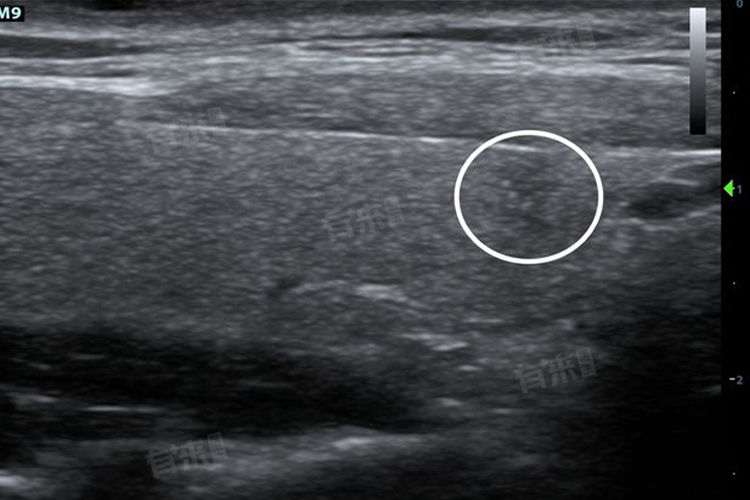

甲状腺4A类是甲状腺结节在超声检查中的一种分类,表示结节有一定的恶性可能。定期进行甲状腺超声检查,监测结节的变化,通过科学的管理和及时的诊治,有助于保障甲状腺的健康。

甲状腺4A类结节可能由多种疾病引起,需要综合评估结节的特征、患者的症状以及其他检查结果来明确诊断,并制定相应的治疗方案。对于甲状腺4A类结节,需要引起重视,但也不必过度恐慌。应遵循医生的建议,进一步进行检查,如穿刺活检等,以明确结节的性质。在日常生活中要注意保持良好的生活习惯,避免过度劳累和精神紧张。饮食方面要均衡营养,避免高碘或低碘饮食。